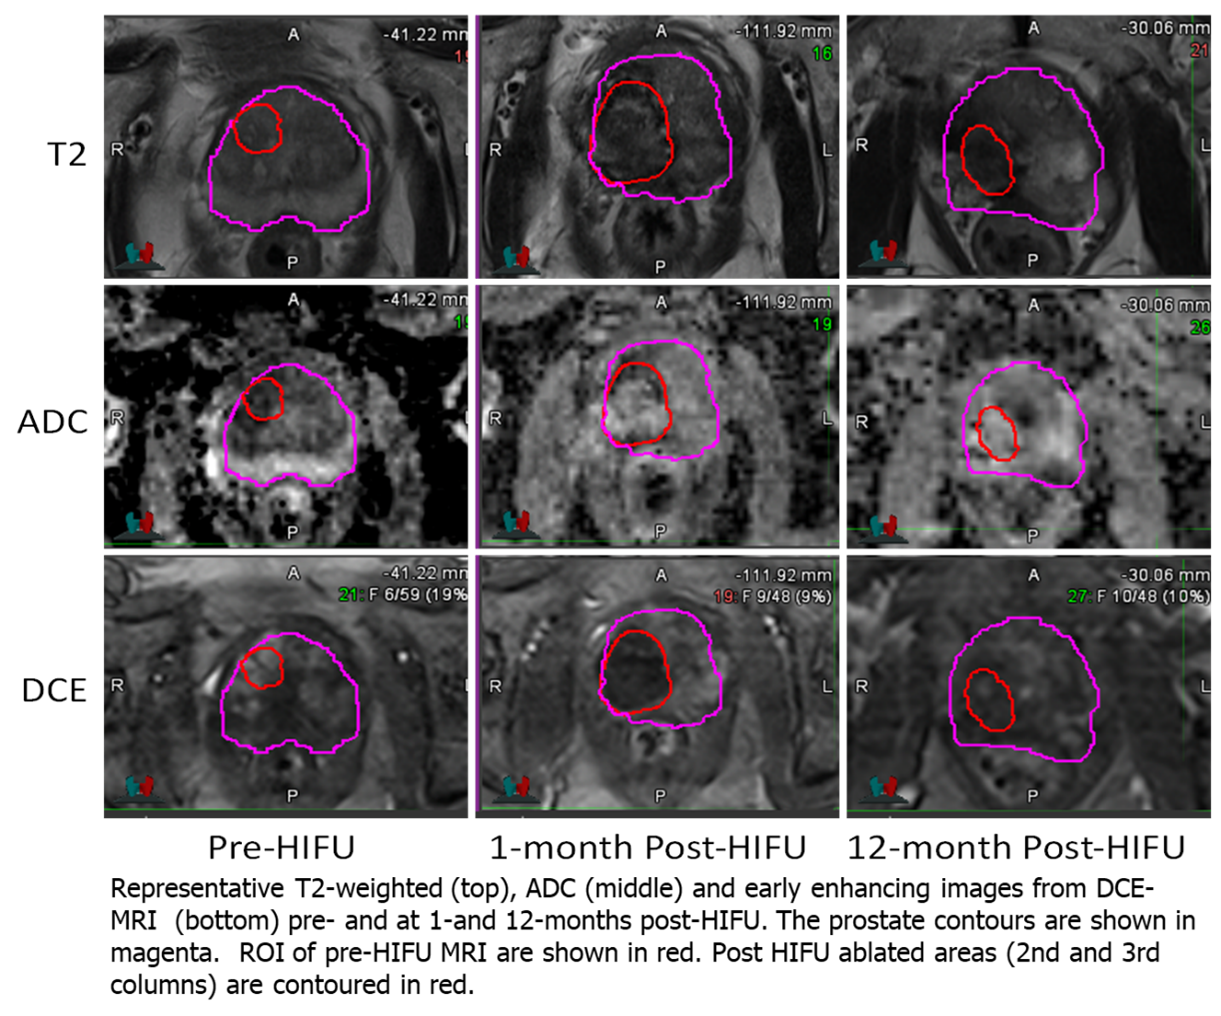

Representative segmentation volumes are illustrated in Figure 2. Pre-treatment ADC values were significantly different between the three volumes: Lesion and NAT-PZ (p<0.001); Lesion and NAT-TZ (p=0.03); and NAT-PZ and NAT-TZ (p<0.001). Lesions had the lowest ADC (mean±SD: 1078±167), followed by NAT_TZ (1190±175) and NAT_PZ (1446±184). Ktrans was also different between the Lesion and NAT-PZ (p<0.001) and NAT-PZ and NAT-TZ (p=0.03). The highest Ktrans was in the Lesion (mean±SD: 0.26±0.11), followed by NAT_TZ (0.20±0.08) and NAT_PZ (mean±SD: 0.15±0.06). The longitudinal changes of ADC and Ktrans before and after HIFU are shown in Figure 3. The most dramatic changes are observed in Ktrans where both 1-month and 12-month post-HIFU measurements are significantly decreased in the ablated zone compared to the pre-treatment lesion (p<0.001). There were no significant changes of Ktrans in NAT-PZ and NAT-TZ. ADC of the ablated zone does not change significantly relative to the pre-HIFU lesion ADC measurement at 1- and 12-month post-operatively (p=0.83 and p=0.07, respectively).

Functional mpMRI changes following HIFU therapy